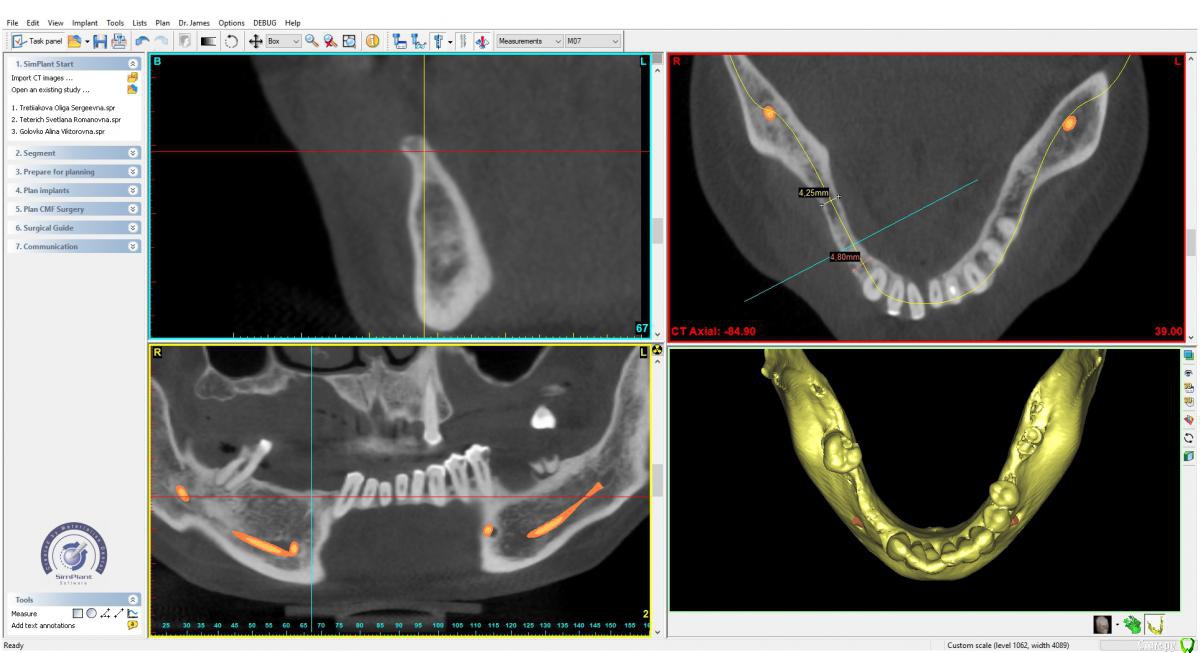

x4ex Опубликовано 28 августа, 2018 Поделиться Опубликовано 28 августа, 2018 (изменено) Здравствуйте, коллеги! Какую методику НКР вы выбрали бы здесь на верхней и нижней челюсти? Варианты: цитопласт, титановая сетка или резорбируемая мембрана (сосидж)? Изменено 28 августа, 2018 пользователем x4ex Ссылка на комментарий

Иван911 Опубликовано 29 августа, 2018 Поделиться Опубликовано 29 августа, 2018 Здравствуйте, коллеги! Какую методику НКР вы выбрали бы здесь на верхней и нижней челюсти? Варианты: цитопласт, титановая сетка или резорбируемая мембрана (сосидж)?tos overview1.jpgtos overview2.jpgЗдравствуйте, я бы выбрал однозначно резорбируемую мембрану, риск осложнений гораздо ниже, а с высотой , вроде как, здесь больших проблем нет. Внутриротовые фото есть ? Ссылка на комментарий

kamranchick Опубликовано 29 августа, 2018 Поделиться Опубликовано 29 августа, 2018 на верхней челюсти возможно я бы поступил без нкр, подгтовил бы ложе компрессионным набором, но с сст.на нижней челюсти, я бы возможно спилил бы узкий участок гребня и тоже без нкр, если пациент пожилой и тоже с сст, бугра хватит на всех) 1 Ссылка на комментарий

Nazim_NV86 Опубликовано 31 августа, 2018 Поделиться Опубликовано 31 августа, 2018 Расщепите верх и через полтора месяца закрутите в +2мм кости. Низ это дилемма. Можно сосидж. Спиливать гребень я бы не стал. Я бы ламину сделал. На финише будет выглядеть лучше. Ссылка на комментарий

Bier Опубликовано 3 сентября, 2018 Поделиться Опубликовано 3 сентября, 2018 наверху вообще пластика не нужна. Только мягкие ткани. Внизу - надо плясать от протетики, а не тупо смотреть на катешечку. Сделайте виртуальный воск (или реальный), соедините его с КТ (или сделать КТ с рентгенконтрастным шаблоном во рту) поставьте имплантаты относительно будущих коронок на 3мм апикальнее и поймете можно ли спилить гребень или не желательно. 3 Ссылка на комментарий

Иван911 Опубликовано 4 сентября, 2018 Поделиться Опубликовано 4 сентября, 2018 наверху вообще пластика не нужна. Только мягкие ткани. Внизу - надо плясать от протетики, а не тупо смотреть на катешечку. Сделайте виртуальный воск (или реальный), соедините его с КТ (или сделать КТ с рентгенконтрастным шаблоном во рту) поставьте имплантаты относительно будущих коронок на 3мм апикальнее и поймете можно ли спилить гребень или не желательно.При 5-ти мм ничего не добавляете? Ссылка на комментарий

Bier Опубликовано 4 сентября, 2018 Поделиться Опубликовано 4 сентября, 2018 При 5-ти мм ничего не добавляете?с минимально откинутым лоскутом имплантаты 3.5, все соединить. Ссылка на комментарий